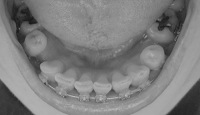

9月末の時点と全然違いがありませんが、一応今日の写真載せときます。